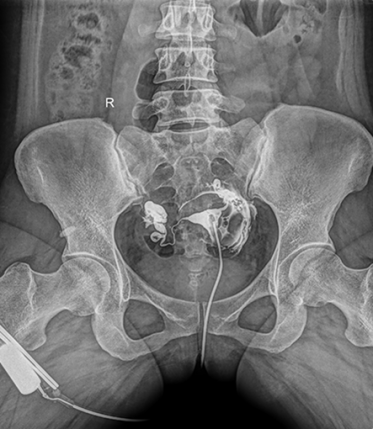

多功能動態(tài)平板DR,采用U型臂結(jié)構(gòu),具有靜態(tài)DR攝影、數(shù)字透視、數(shù)字造影和可視化攝影的功能。

電動旋轉(zhuǎn)內(nèi)平衡結(jié)構(gòu),可實(shí)現(xiàn)快捷擺位,滿足特殊體位的靜態(tài)與動態(tài)檢查。

● 可快速選擇、預(yù)設(shè)所需要的視野,節(jié)約擺位時(shí)間;

● 根據(jù)拍攝需求或技師使用習(xí)慣一鍵切換光束范圍;

● 可根據(jù)不同的體位協(xié)議,自動調(diào)整光束大小。